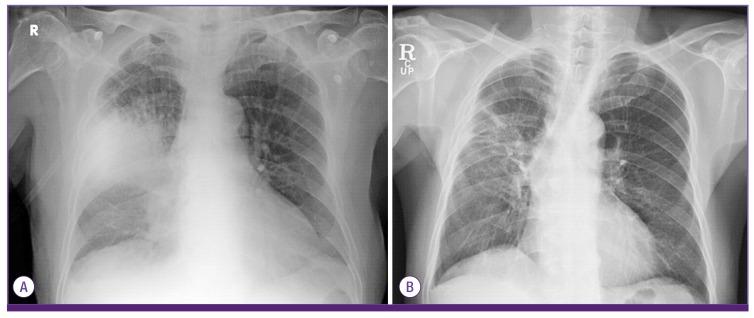

韩国一例由多重耐药鲍曼不动杆菌引起的社区获得性肺炎病例。

A Case of Community-Acquired Pneumonia Caused by Multidrug-Resistant Acinetobacter baumannii in Korea.

Acinetobacter baumannii is an aerobic Gram-negative coccobacillus that causes nosocomial pneumonia in patients on mechanical ventilation or previously treated with broad-spectrum antibiotics. Nevertheless, community-acquired pneumonia (CAP) caused by A. baumannii, especially multi-drug resistant (MDR) strains, is rare. We experienced the first case of CAP caused by MDR A. baumannii in Korea in a 78-year-old man. This case shows that MDR A. baumannii can cause CAP in Korea.

鲍曼不动杆菌是一种需氧革兰氏阴性球杆菌,可导致接受机械通气或先前接受过广谱抗生素治疗的患者发生医院获得性肺炎。然而,由鲍曼不动杆菌引起的社区获得性肺炎(CAP),尤其是多重耐药(MDR)菌株引起的情况很少见。我们在韩国遇到了首例由多重耐药鲍曼不动杆菌引起的社区获得性肺炎病例,患者为一名78岁男性。该病例表明,多重耐药鲍曼不动杆菌在韩国可引起社区获得性肺炎。